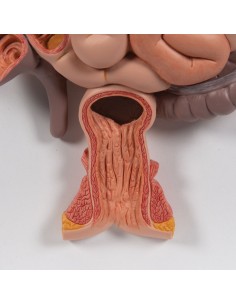

Dal cranio in 22 parti con incastri magnetici ai modelli di colonna vertebrale, da quelli di articolazioni a quelli di cuore, ogni pezzo della nostra collezione è progettato per un’immersione totale nello studio dell’anatomia umana. I nostri modelli, realizzati tramite scansioni di ossa vere, garantiscono un’esperienza tattile autentica e una fedeltà di peso quasi identica agli originali.

Essenziali per studenti e professionisti, i nostri modelli anatomici sono strumenti didattici che permettono di osservare le strutture anatomiche con precisione, eliminando la necessità di dissezioni o studi invasivi. Sono inoltre utili per spiegare ai pazienti le patologie, rendendo la comunicazione più efficace e risparmiando tempo prezioso.